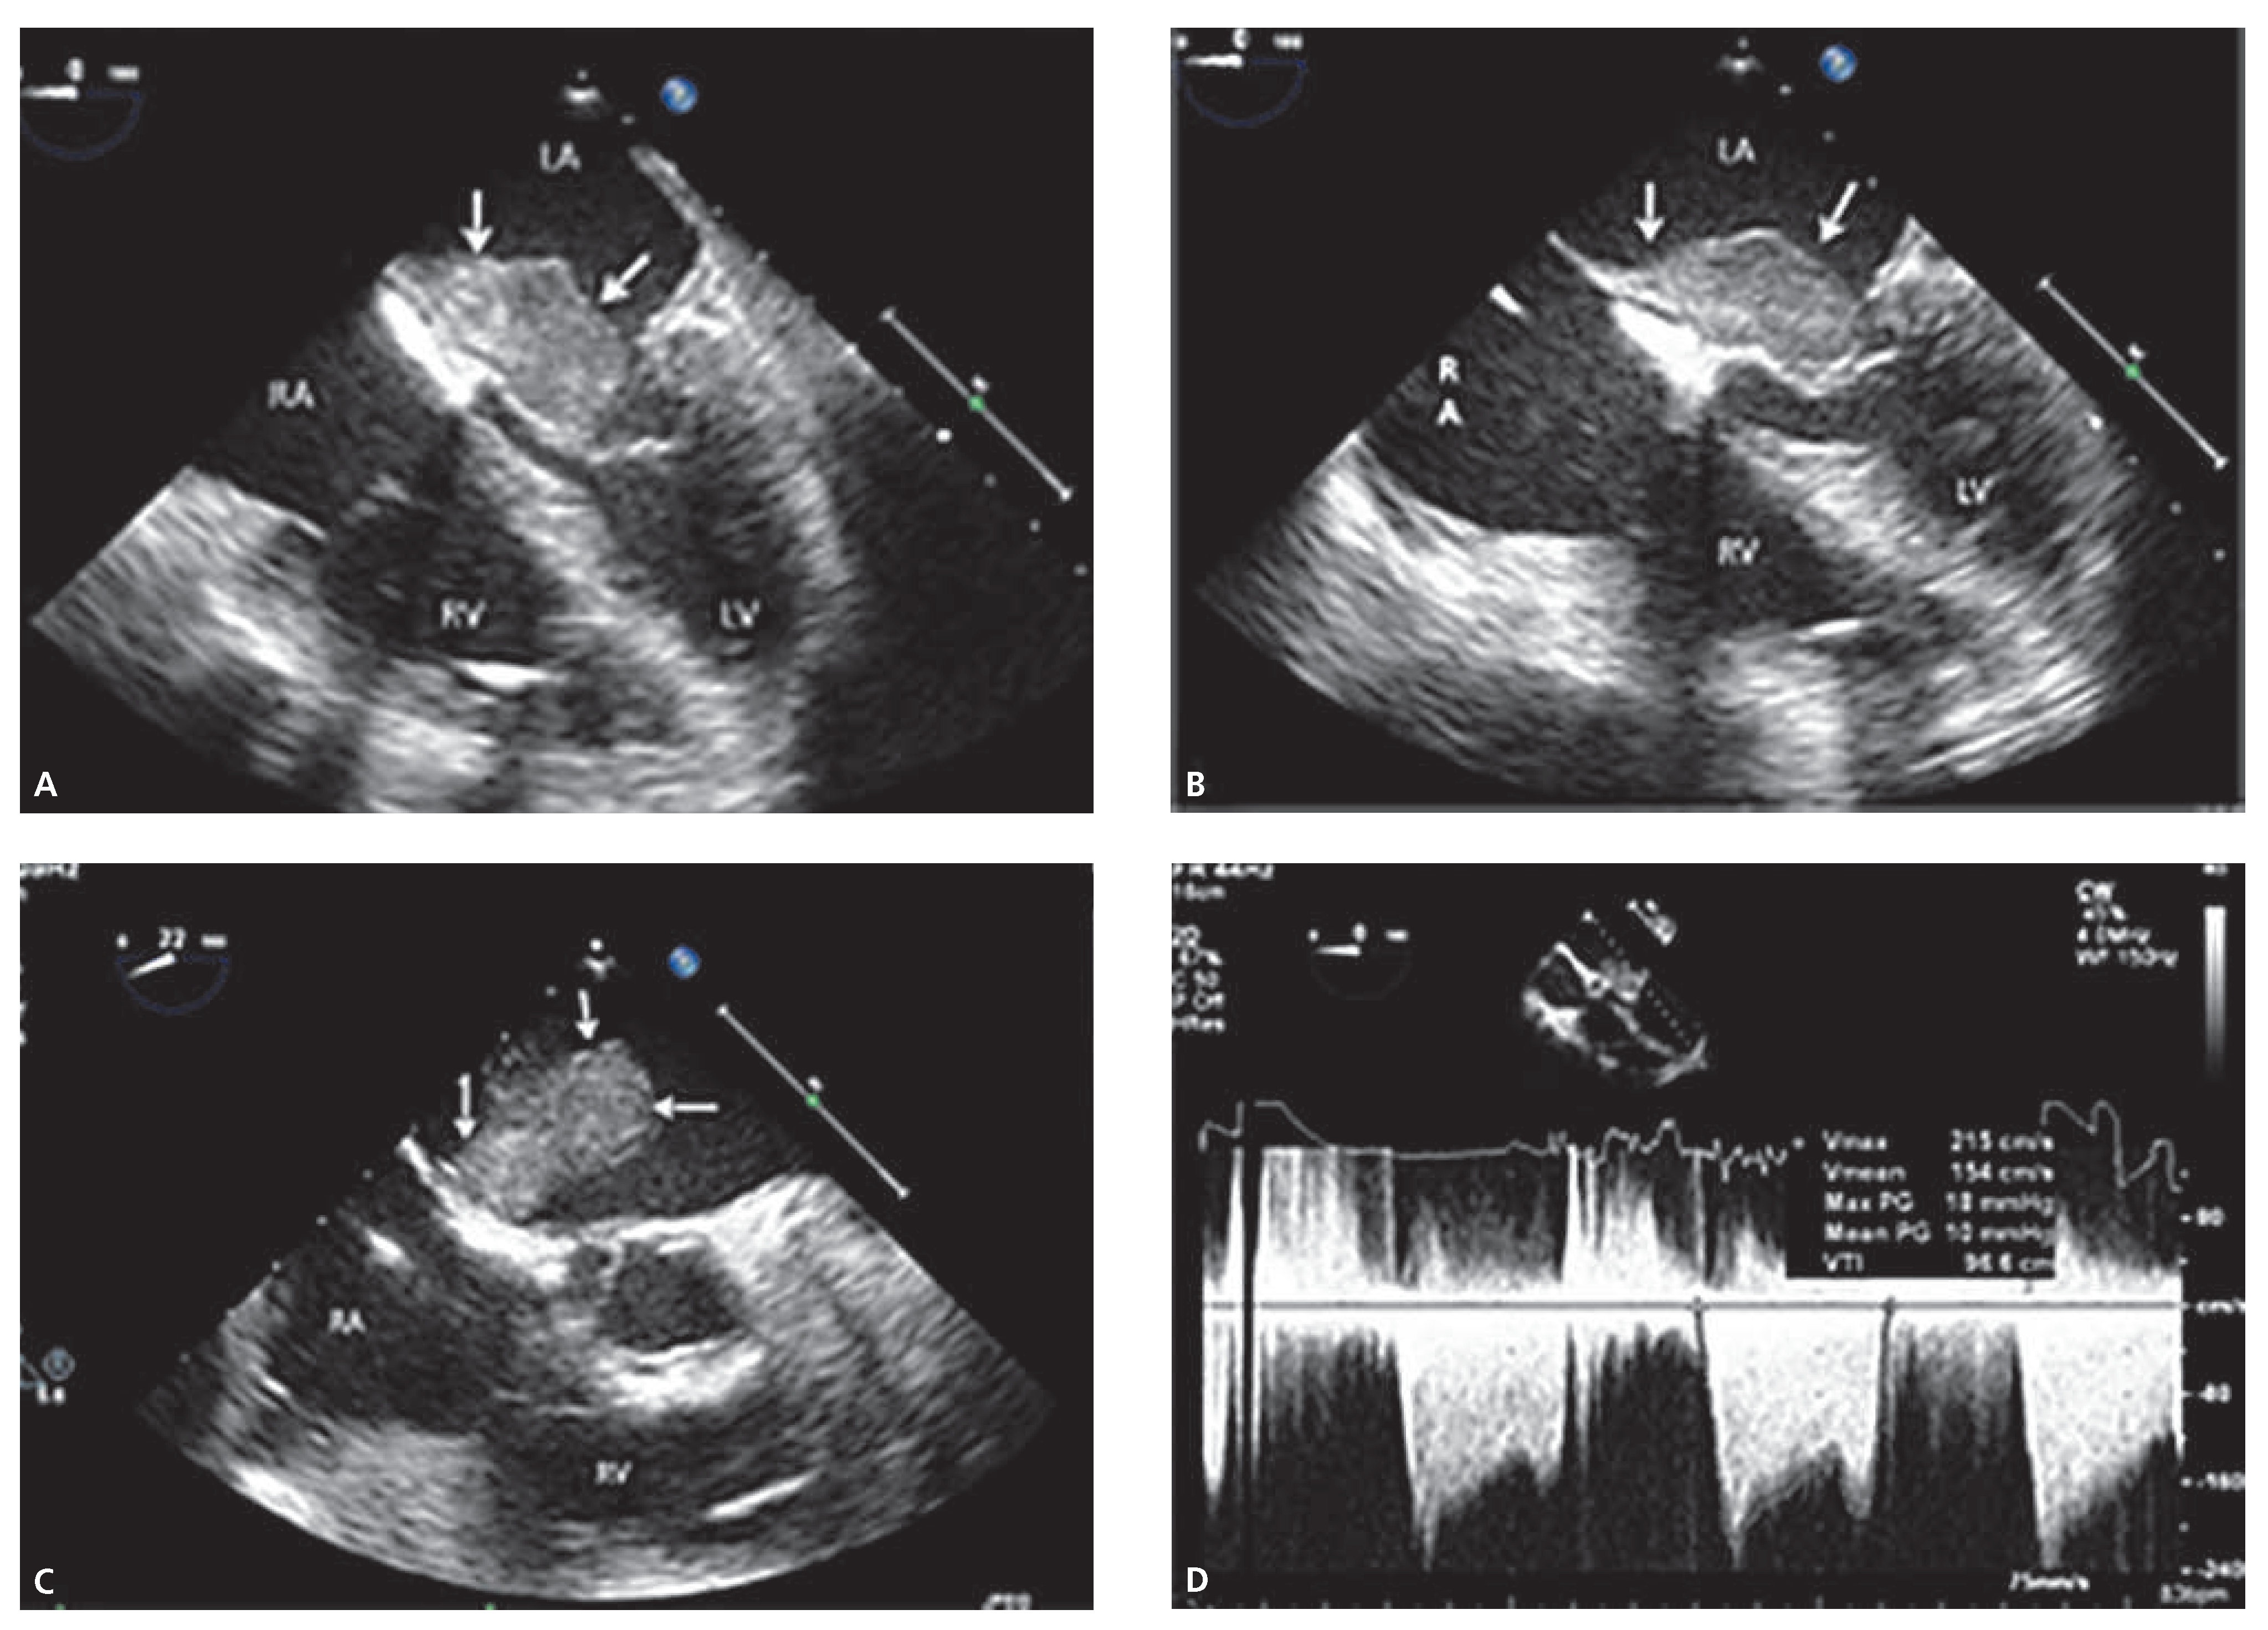

Atrial Myxoma Resulting in Severe Mitral Stenosis